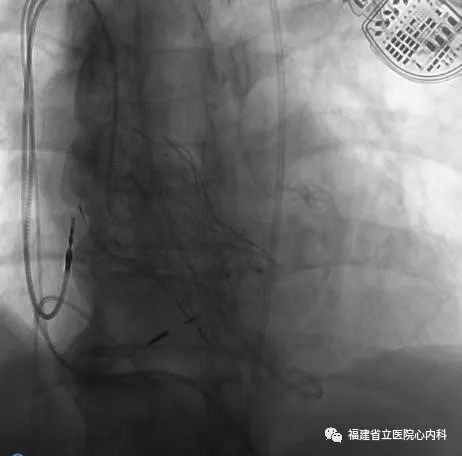

病例5

该病例是功能性二叶瓣,瓣叶增厚,重度钙化,左无钙化融合,形成明显瓣上限制结构,同时合并横位心,对于瓣膜的定位及锚定增加了一定难度,手术过程术者们精细操作,稳定释放,最终26号瓣膜精准定位,成功解除患者的狭窄问题,术后患者症状改善明显。

瓣环

窦部

球囊预扩张

植入L26瓣膜